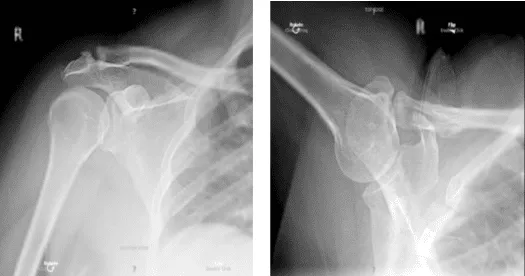

The patient is a 54-year-old female who came into the office after falling and being unable to move her shoulder. She was in a lot of discomfort. The examination revealed a rotator cuff tear. An MRI revealed a significant rotator cuff tear in the left shoulder as well as a biceps subluxation.

X-ray bilateral shoulders